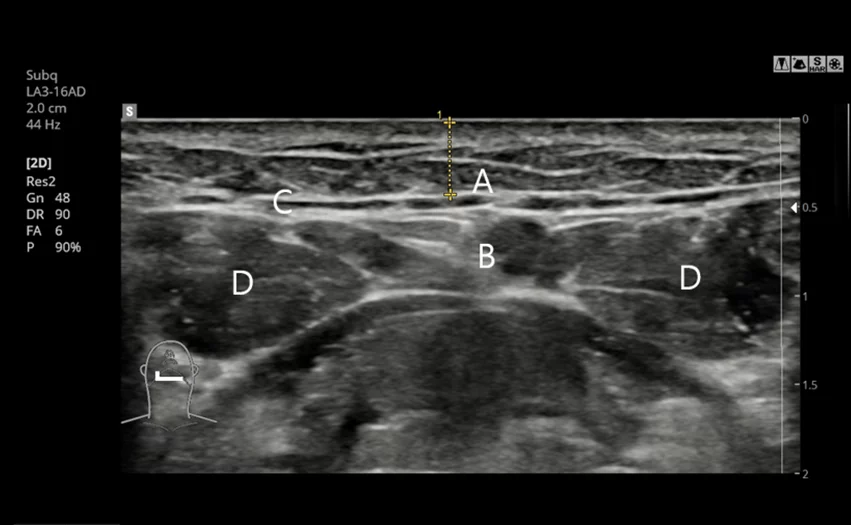

5. Precise pre-surgical diagnosis with CT and ultrasound

Through CT scans and ultrasound examinations, AB precisely analyzes the location and size of the salivary glands, enabling delicate and customized gland removal surgery when necessary